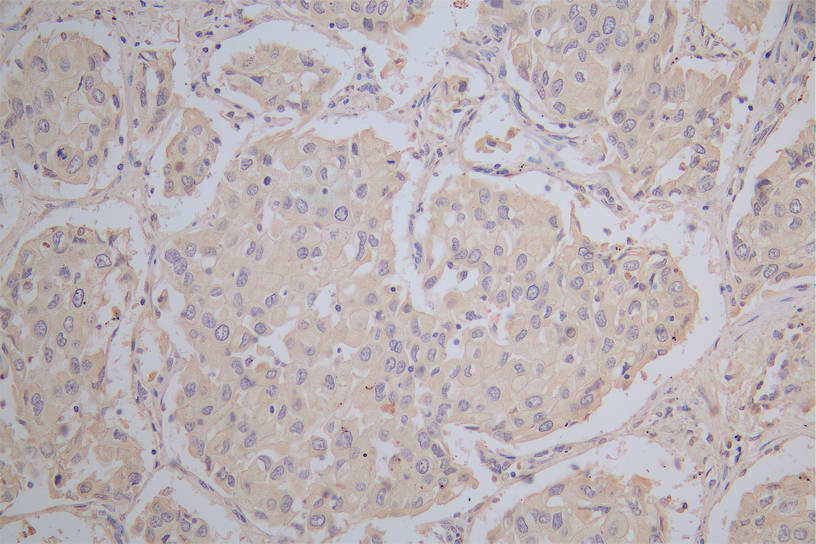

IHC image of CSB-RA878942MA1HU diluted at 1:100 and staining in paraffin-embedded human lung cancer performed on a Leica BondTM system. After dewaxing and hydration, antigen retrieval was mediated by high pressure in a citrate buffer (pH 6.0). Section was blocked with 10% normal goat serum 30min at RT. Then primary antibody (1% BSA) was incubated at 4°C overnight. The primary is detected by a Goat anti-Mouse IgG labeled by HRP and visualized using 0.05% DAB.